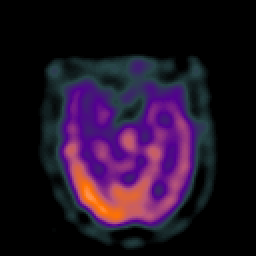

Subacute Stroke overlay -- Slice #9

[Home][Help][Clinical] Slice 9